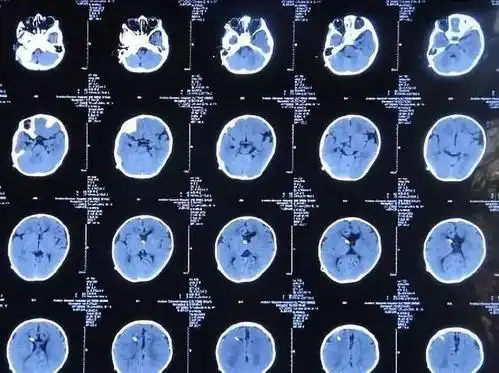

收藏!影像医生必备 | 手把手教你读懂颅脑ct

67超急性期大面积脑梗死ct平扫表现

皓月ct头颅图像技术和样片分享